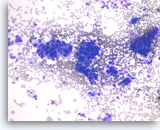

Ductal adenocarcinoma #1,

Pancreas FNA, Direct Smear.

The aspirates show single and clusters of malignant epithelial cells. The clusters are three-dimensional with overlapped nuclei. A few histiocytes are seen in the background.

20X